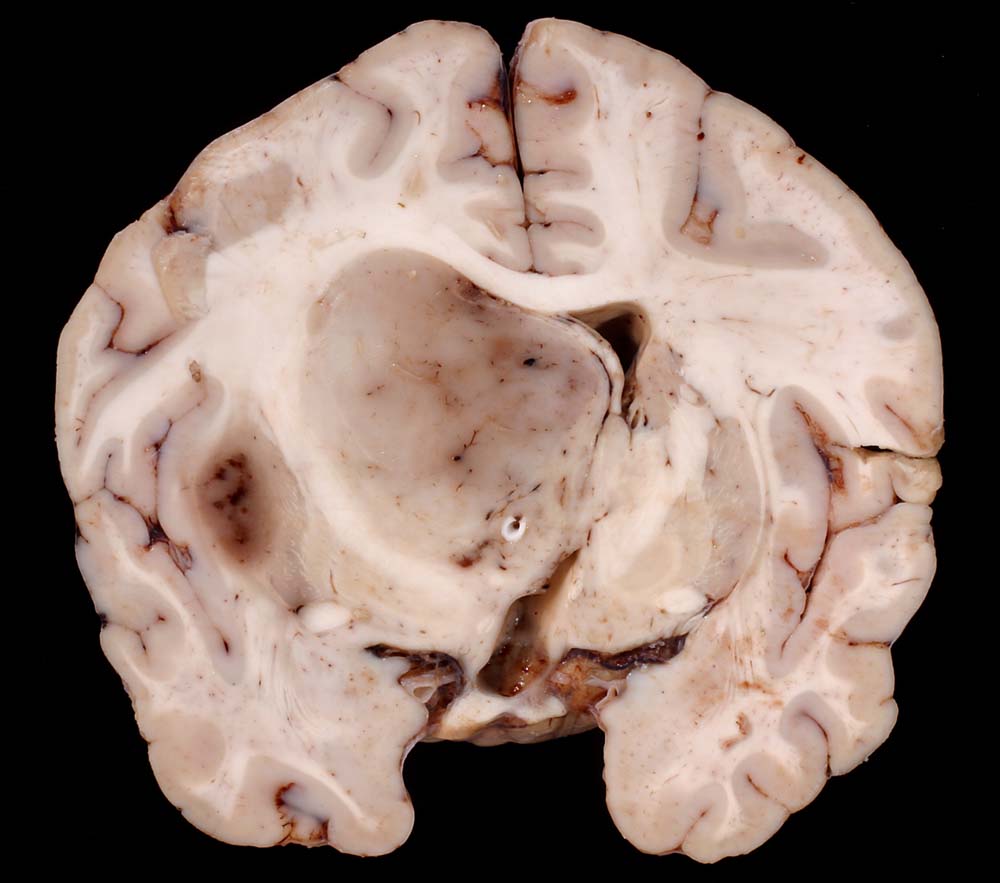

Die meisten Tumoren sind solitär und kortikal oder subkortikal in einer Grosshirnhemisphäre lokalisiert, am häufigsten frontal. Gelegentlich können sie primär intraventrikulär auftreten.

Makroskopisch sind die Tumoren gut begrenzt, solide und graurosa. Fokale Verkalkungen sind häufig, Nekrosen und zystische Degeneration können vorkommen. Intratumorale Einblutungen sind oft vorhanden und können die Todesursache darstellen.